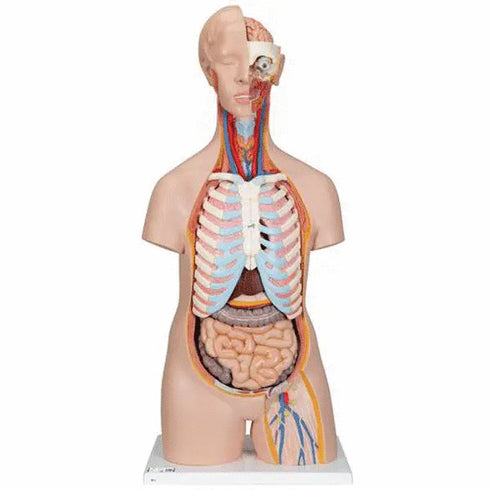

Trunchiul uman anatomic corect format din 16 parti este un instrument educational de inalta calitate. Trunchiul unisex este pictat manual, fidel detaliilor, si este fabricat din plastic de inalta calitate.

Acest tors uman clasic a fost dezvoltat si modelat in Germania. Indiferent daca sunteti student la anatomia umana intr-o clasa de biologie sau doctor care explica ceva unui pacient, acest model de tors uman este un instrument valoros.

Urmatoarele componente ale acestui tors unisex sunt detasabile:

- cap (3 parti);

- plamani cu stern si coaste (2 parti);

- inima (2 parti);

- stomacul;

- ficatul cu vezica biliara;

- tract intestinal (4 parti);

- jumatatea din fata a rinichiului;

- jumatatea din fata a vezicii urinare.

Caracteristici tehnice:

• dimensiuni: 87 x 38 x 25 cm;

• greutate: 8.473 kg.